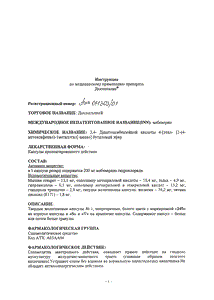

Инструкция по применению дюспаталина

Краткое описание

Дюспаталин (действующее вещество мебеверин) — спазмолитическое средство, используемое в гастроэнтерологической практике при разного рода болях, спастических явлениях и ощущении дискомфорта в кишечнике. Препарат оказывает прямое миотропное действие на гладкомышечный каркас желудочно-кишечного тракта (прежде всего — толстого кишечника). В основе реализации фармакологического эффекта дюспаталина лежит блокада натриевых каналов в мембране мышечных клеток (вследствие чего нарушается проникновение в них ионов натрия и кальция), угнетение процессов деполяризации мембраны, что в конечном итоге препятствует сокращениям мышц. На этом фоне происходит расслабление гладкой мускулатуры пищеварительного тракта и устранение спазмов. Что же касается нормальной перистальтики кишечника, то препарат не оказывает на нее ровным счетом никакого влияния, что, конечно же, является его неоспоримым достоинством. Антихолинэргическим действием дюспаталин не наделен.

Дюспаталин выпускается только в лекарственных формах для внутреннего применения: в таблетках и капсулах, которые следует принимать целиком вместе с достаточным количеством жидкости. Стандартный график приема дюспаталина: 1 капсула/таблетка трижды в день (в капсулах — дважды в день) за 20 минут до приема пищи.

Каких-либо ограничений продолжительности приема препарата нет. Если по определенным причинам плановый прием препарата был пропущен, не следует «отыгрываться», принимая за один раз сразу несколько разовых доз. В данном случае рекомендуется продолжить прием дюспаталина в обычном режиме.

Препарат практически не имеет противопоказаний. Данное утверждение справедливо и в отношении его приема в период беременности и грудного вскармливания, однако в данном случае врачи делают оговорку, что всегда необходимо соотносить ожидаемую пользу от приема препарата для матери и потенциальные риски возникновения непредвиденных побочных эффектов для плода. В любом случае последнее решение должно быть за специалистом. Что же касается лактации (грудного вскармливания), то применение дюспаталина в этот период не влечет за собой никакой угрозы, т.к. препарат не способен проникать в грудное молоко. Случаи передозировки дюспаталина в медицинской литературе к настоящему моменту не описывались, однако в подобных случаях теоретически возможно повышение реактивности центральной нервной системы. В данных ситуациях показано промывание кишечника и терапевтическая коррекция симптомов передозировки.

Фармакология

Спазмолитик миотропного действия. Оказывает прямое действие на гладкую мускулатуру ЖКТ. Устраняет спазм без влияния на нормальную перистальтику кишечника.

Не обладает антихолинергическим действием.